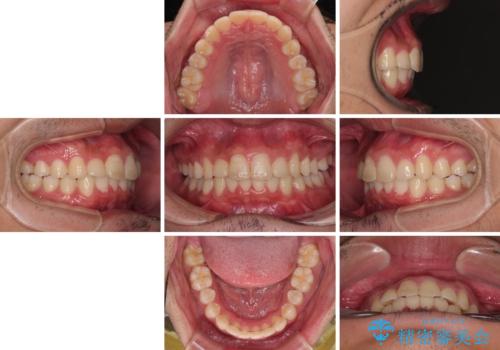

補助装置を併用せずに治療を終える可能性はありましたが、確実に結果を得るために補助装置を活用しました。

イメージしたとおりの仕上がりとなりました。